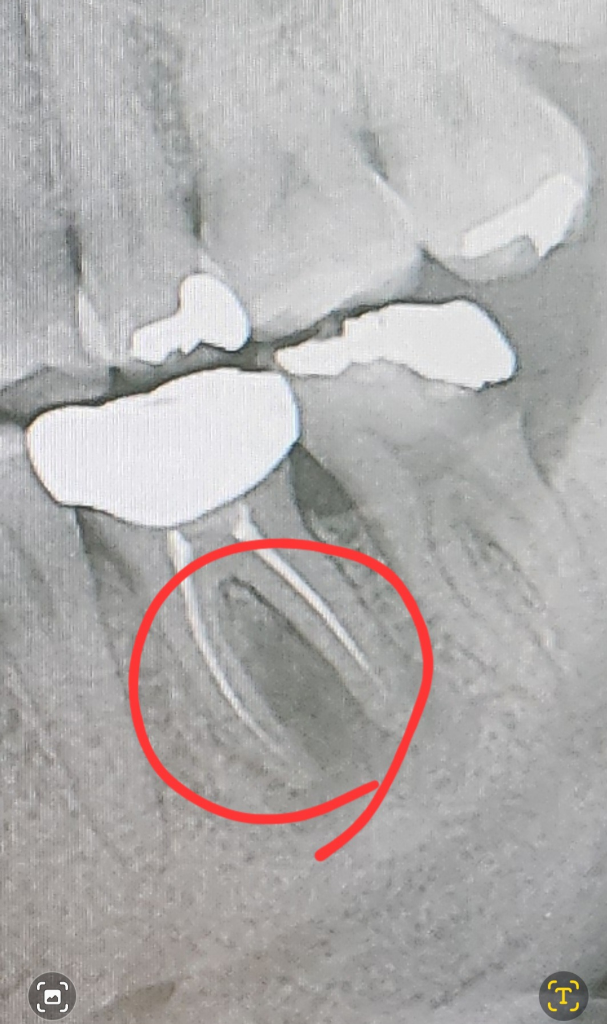

치과 치료에 대한 질문이시군요.

해당 질문은 치과 카테고리에 작성하시면 더 정확한 답변을 받아보실 수 있을 것 같습니다.